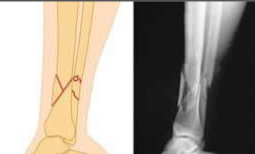

What type of fracture is this?

Spiral fracture

more common in younger age